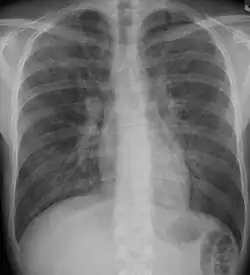

A chest x-ray is 63% sensitive and 93% specific for ILD.[10] With advances in computed tomography, CT scans of the chest have supplanted lung biopsy as the preferred diagnostic test for ILD. A thoracic CT scan is 91% sensitive and 71% specific for ILD.[10] In higher income countries, less than 10% of people with ILD undergo a lung biopsy as part of the diagnostic evaluation.[16]

Chest radiography is usually the first test to detect interstitial lung diseases, but the chest radiograph can be normal in up to 10% of patients, especially early in the disease process.[19][20]

High-resolution CT of the chest is the preferred modality and differs from routine CT of the chest. Conventional (regular) CT chest examines 7–10 mm slices obtained at 10 mm intervals; high resolution CT examines 1–1.5 mm slices at 10 mm intervals using a high-spatial-frequency reconstruction algorithm. The HRCT therefore provides approximately 10 times more resolution than the conventional CT chest, allowing the HRCT to elicit details that cannot otherwise be visualized.[19][21]

Radiologic appearance alone, however, is not adequate and should be interpreted in the clinical context, keeping in mind the temporal profile of the disease process.[19]